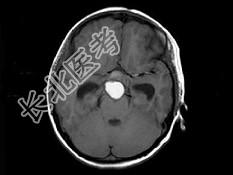

- 单项选择题男,15岁, 2个月前无明显诱因出现头痛,间断性钝痛, 根据所提供图像,最可能的诊断是 ( )

A、垂体瘤

B、颅咽管瘤(造釉细胞型)

C、生殖细胞瘤

D、胶质细胞瘤

E、结核性肉芽肿